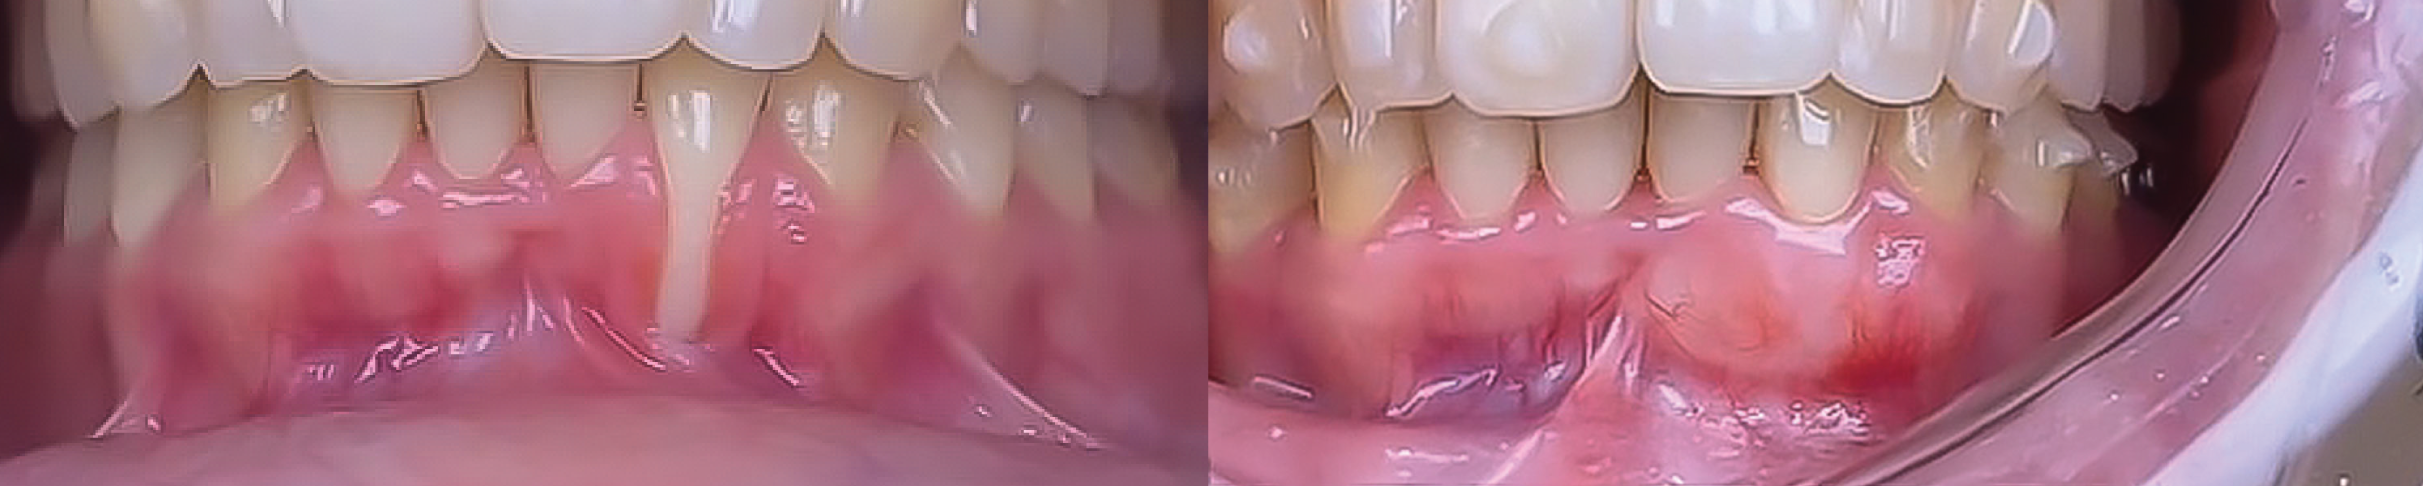

Soft tissue management and Tunnel Techniques. This two-day intensive course will provide participants with both theoretical foundations and practical experience in periodontal plastic surgery.

Through lectures, clinical case discussions, and hands-on practice, participants will learn advanced surgical techniques for root coverage, soft tissue grafting, and esthetic enhancement in periodontal procedures.

Soft tissue management and Tunnel Techniques. This two-day intensive course will provide participants with both theoretical foundations and practical experience in periodontal plastic surgery.

Through lectures, clinical case discussions, and hands-on practice, participants will learn advanced surgical techniques for root coverage, soft tissue grafting, and esthetic enhancement in periodontal procedures.

Coronally Advanced Flap for Isolated Recessions -Subepithelial Connective Tissue Graft |

Coronally Advanced Flap for Multiple Recessions -Subepithelial Connective Tissue Graft |